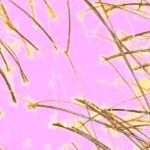

- Tricoscopía/capilografía y exámenes complementarios, si es necesario, para identificar el tipo de alopecia.

Utiliza luz LED de espectro específico para estimular el metabolismo celular, reducir la inflamación y favorecer el crecimiento de cabello más fuerte y saludable. - Tricoscopía. Examen médico no invasivo que permite observar en detalle el cuero cabelludo y los folículos pilosos mediante un dermatoscopio digital.

IMÁGENES EXAMEN CAPILAR